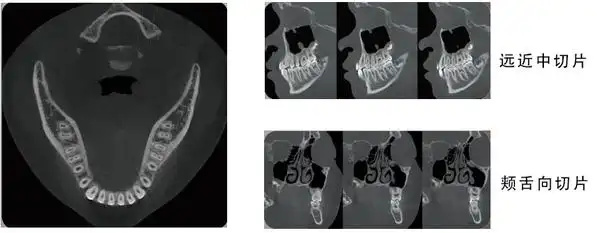

42和43)和双生牙(17)(cbct图);a 为轴位;b 为矢状位;c 为3d图像;d 为